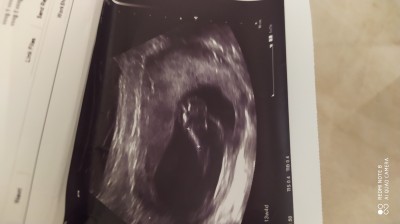

Kızlar burda ultrason resminde bebek nerde cinsiyyət gozukuyomu cinsiyyət soyledi doktor ama bu fotoda bebeyim nerde anlayamadim

18 haftalik canım erkek dedi doktor resimden bir şey anlamadım o yüzden sordum

Bilemiyorum canım 11 haftada da 14 de simdi de erkek dedi iki farklı doktor bizde sürpriz filan hazırladıq ben kesinmi diye sordum kesin dedi cinsiyyət deyisirmi dedim bana senin karninda deyismez ama dogdukdan sonra cinsiyetini  deyisirmi bilemem dedi sakayla o kadar sordum ki kesinmi diye o yüzden